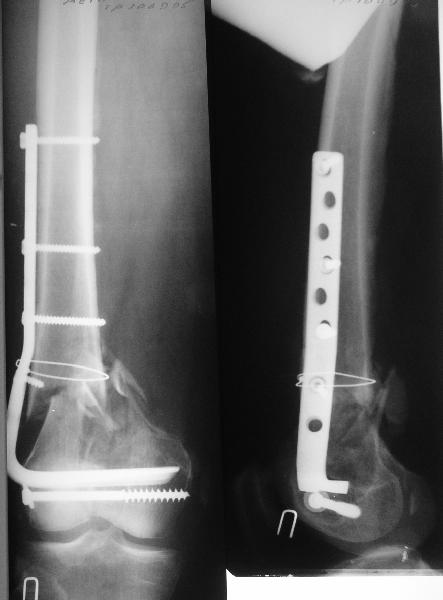

Удалили ластину без проблем. Выявилась значительная подвижность. В этих условиях сразу пропала мотивация к постепенной коррекции аппаратом. Попробовал восстановить длину, введя между отломками spreader. Отчасти удалось. Тогда защили рану, наложили спицевой дистрактор (2 спицы в дистальный отдел и 1 вверху). после этого был убран и спонгиозный винт. И сделали антгерадное штифтование, как говорится, "по принятой в

клинике методике".

С.Максимов:

> При остеосинтезе гвоздем кроме доступа для удаления пластины и

> репозиции необходим дополнительный доступ и дополнительная травма

> сустава (?).

Дополнительные доступы для введения гвоздя и проксимальных винтов понадобились, но они маленькие, по 1 см. Нижние винты ввели прямо между швами. Суставы дополнительно не травмировали, и даже ввели гвоздь не через f. piriformis, а через большой вертел.

Длину восстановили, возможно, даже с изьбытком, ну да динамизируем пораньше. Введенные в овальное отверстие дистальые винты имеют угловую стабильность. Снимки приложены. Заранее спасибо за критику и комментарии.